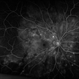

- A 45-year-old female presented with complaints of gradual loss of vision before 3 months and when reached to hospital had this picture.